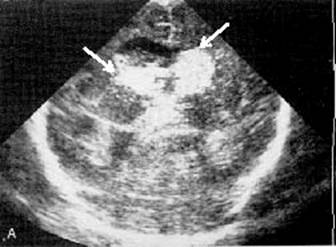

Grade III extension with dilatation (coronal view).